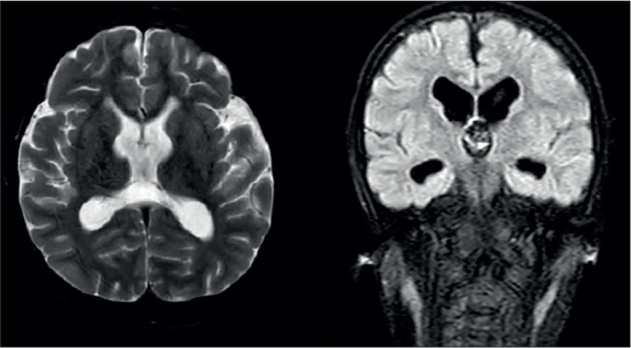

Raynaud-Claes syndrome is rare condition characterized with intellectual disability and is caused by X-linked pathogenic variants in CLCN4 gene. Hemizygous missense variant NM_001830.4: c.1597G>A (p.V533M) was detected in a 6-year-old male followed up with intellectual disability, dysmorphism, and epileptic encephalopathy. The mother and one sister of the patient were also carrying the same variant. The clinical picture of the patient was significantly more severe, and the patient exhibited nonconvulsive status. Tonic status was observed with benzodiazepine treatment and the patient was successfully treated with a ketogenic diet. Many types of seizures can be seen in Raynaud-Claes syndrome, some of which can be life-threatening. CLCN4 variants can be investigated in patients who exhibit an increase in tonic seizures with benzodiazepine treatment. However, ketogenic dietary therapy as first-line treatment can be lifesaving in resistant epilepsy cases caused by the CLCN4 gene.